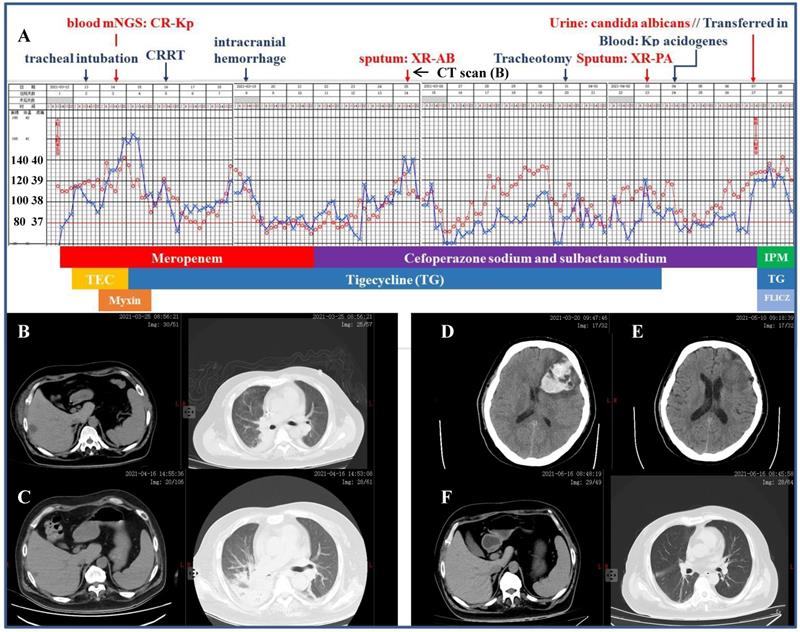

Severe infection caused by the CR-Kp

A 41-year-old diabetic man was referred to our ICU for a 2-day's history of fever pegging at 38.5 ºC and dyspnea, which was preceded by rigor (Figure 2). According to the workup on admission including CT scan which detected pulmonary infection and hepatic abscess, the initial diagnosis was septic shock, liver abscess and multiple organs dysfunction comprising of circulatory, respiratory and renal failure, type 2 diabetes and thrombocytopenia (platelet 38×109/L, reference 100-300×109/L). Mechanical ventilation, mNGS of the blood (with CR-Kp subsequently identified) and CRRT were initiated in short notice. The antibiotic make-up was composed of meropenem followed by cefoperazone sodium and sulbactam sodium, mainly accompanied by tigecycline. However, the patient remained febrile and his condition was further complicated by intracranial hemorrhage, isolation of multiple drug-resistant Acinetobacter baumannii and Pseudomonas aeruginosa from the sputum, Kp acidogenes from the blood, and Candidas albicans from the urine. He was then transferred to our department after a 26-day stay in the ICU, with the temperature still fluctuating around 39.0 ºC and more pronounced right segmental atelectasis. Our antibiotic regimens included three consecutive packages as following: ceftazidime avibactam sodium, aztreonam and fluconazol for 23 days, imipenem and amikacin (aerosol inhalation) for 23 days, and amoxicillin potassium clavulanate and minocycline for 3 days until discharge. Reassuringly, the patient's temperature returned to normal two days after the application of ceftazidime avibactam sodium regimen and remained so thereafter. When discharged, the patient had platelet count of 312×109/L and serum creatinine of 48.7 µmol/L (reference 57.0-97.0 µmol/L), without discernible pulmonary, hepatic and intracranial lesions.

Figure 2

Clinical course and imaging findings in the patient with CR-Kp infection. Part-1 Management of the patient prior to his transferring to our department. A: Major therapeutic procedures during the patient's hospital stay. Red dots and blue cross indicated the patient's heart rate and temperature, respectively. Joint antibiotics use was at the bottom of the panel. B: CT scan 2-week after admission showing pulmonary infection and hepatic abscess. C: CT scan 12-day after the patient was transferred in showing right segmental atelectasis and significantly reduced hepatic abscess. D and E: CT scans immediately after the onset of cerebral hemorrhage and 2-week prior to his discharge, respectively. F: CT scan 10-day shortly before the discharge. Part-2 Management of the patient after his transferring to our department. A (continued): Major therapeutic procedures and joint antibiotics use at the bottom of the panel. G: accessory genes by which the four distinct Kp strains were genetically defined (adapted from Ref. 5 by Martin RM et al., Front Cell Infect Microbiol. 2018) H: comparison of the β-lactamase inhibitors and spectrum of inhibition. (adapted from Ref. 25 by Bush K et al., Nat Rev Microbiol. 2019) mNGS: metagenomics next generation sequencing. CRRT: continuous renal replacement therapy. XR-AB and XR-PA: multiple drug resistance Acinetobacter baumannii and Pseudomonas aeruginosa, respectively. HD: hemodialysis. TEC: teicoplanin. IPM: imipenem. FLICZ: fluconazol. DBO: diazabicyclooctanone analogue. ESBL: extended-spectrum β-lactamase. MBL: metallo-β-lactamase.